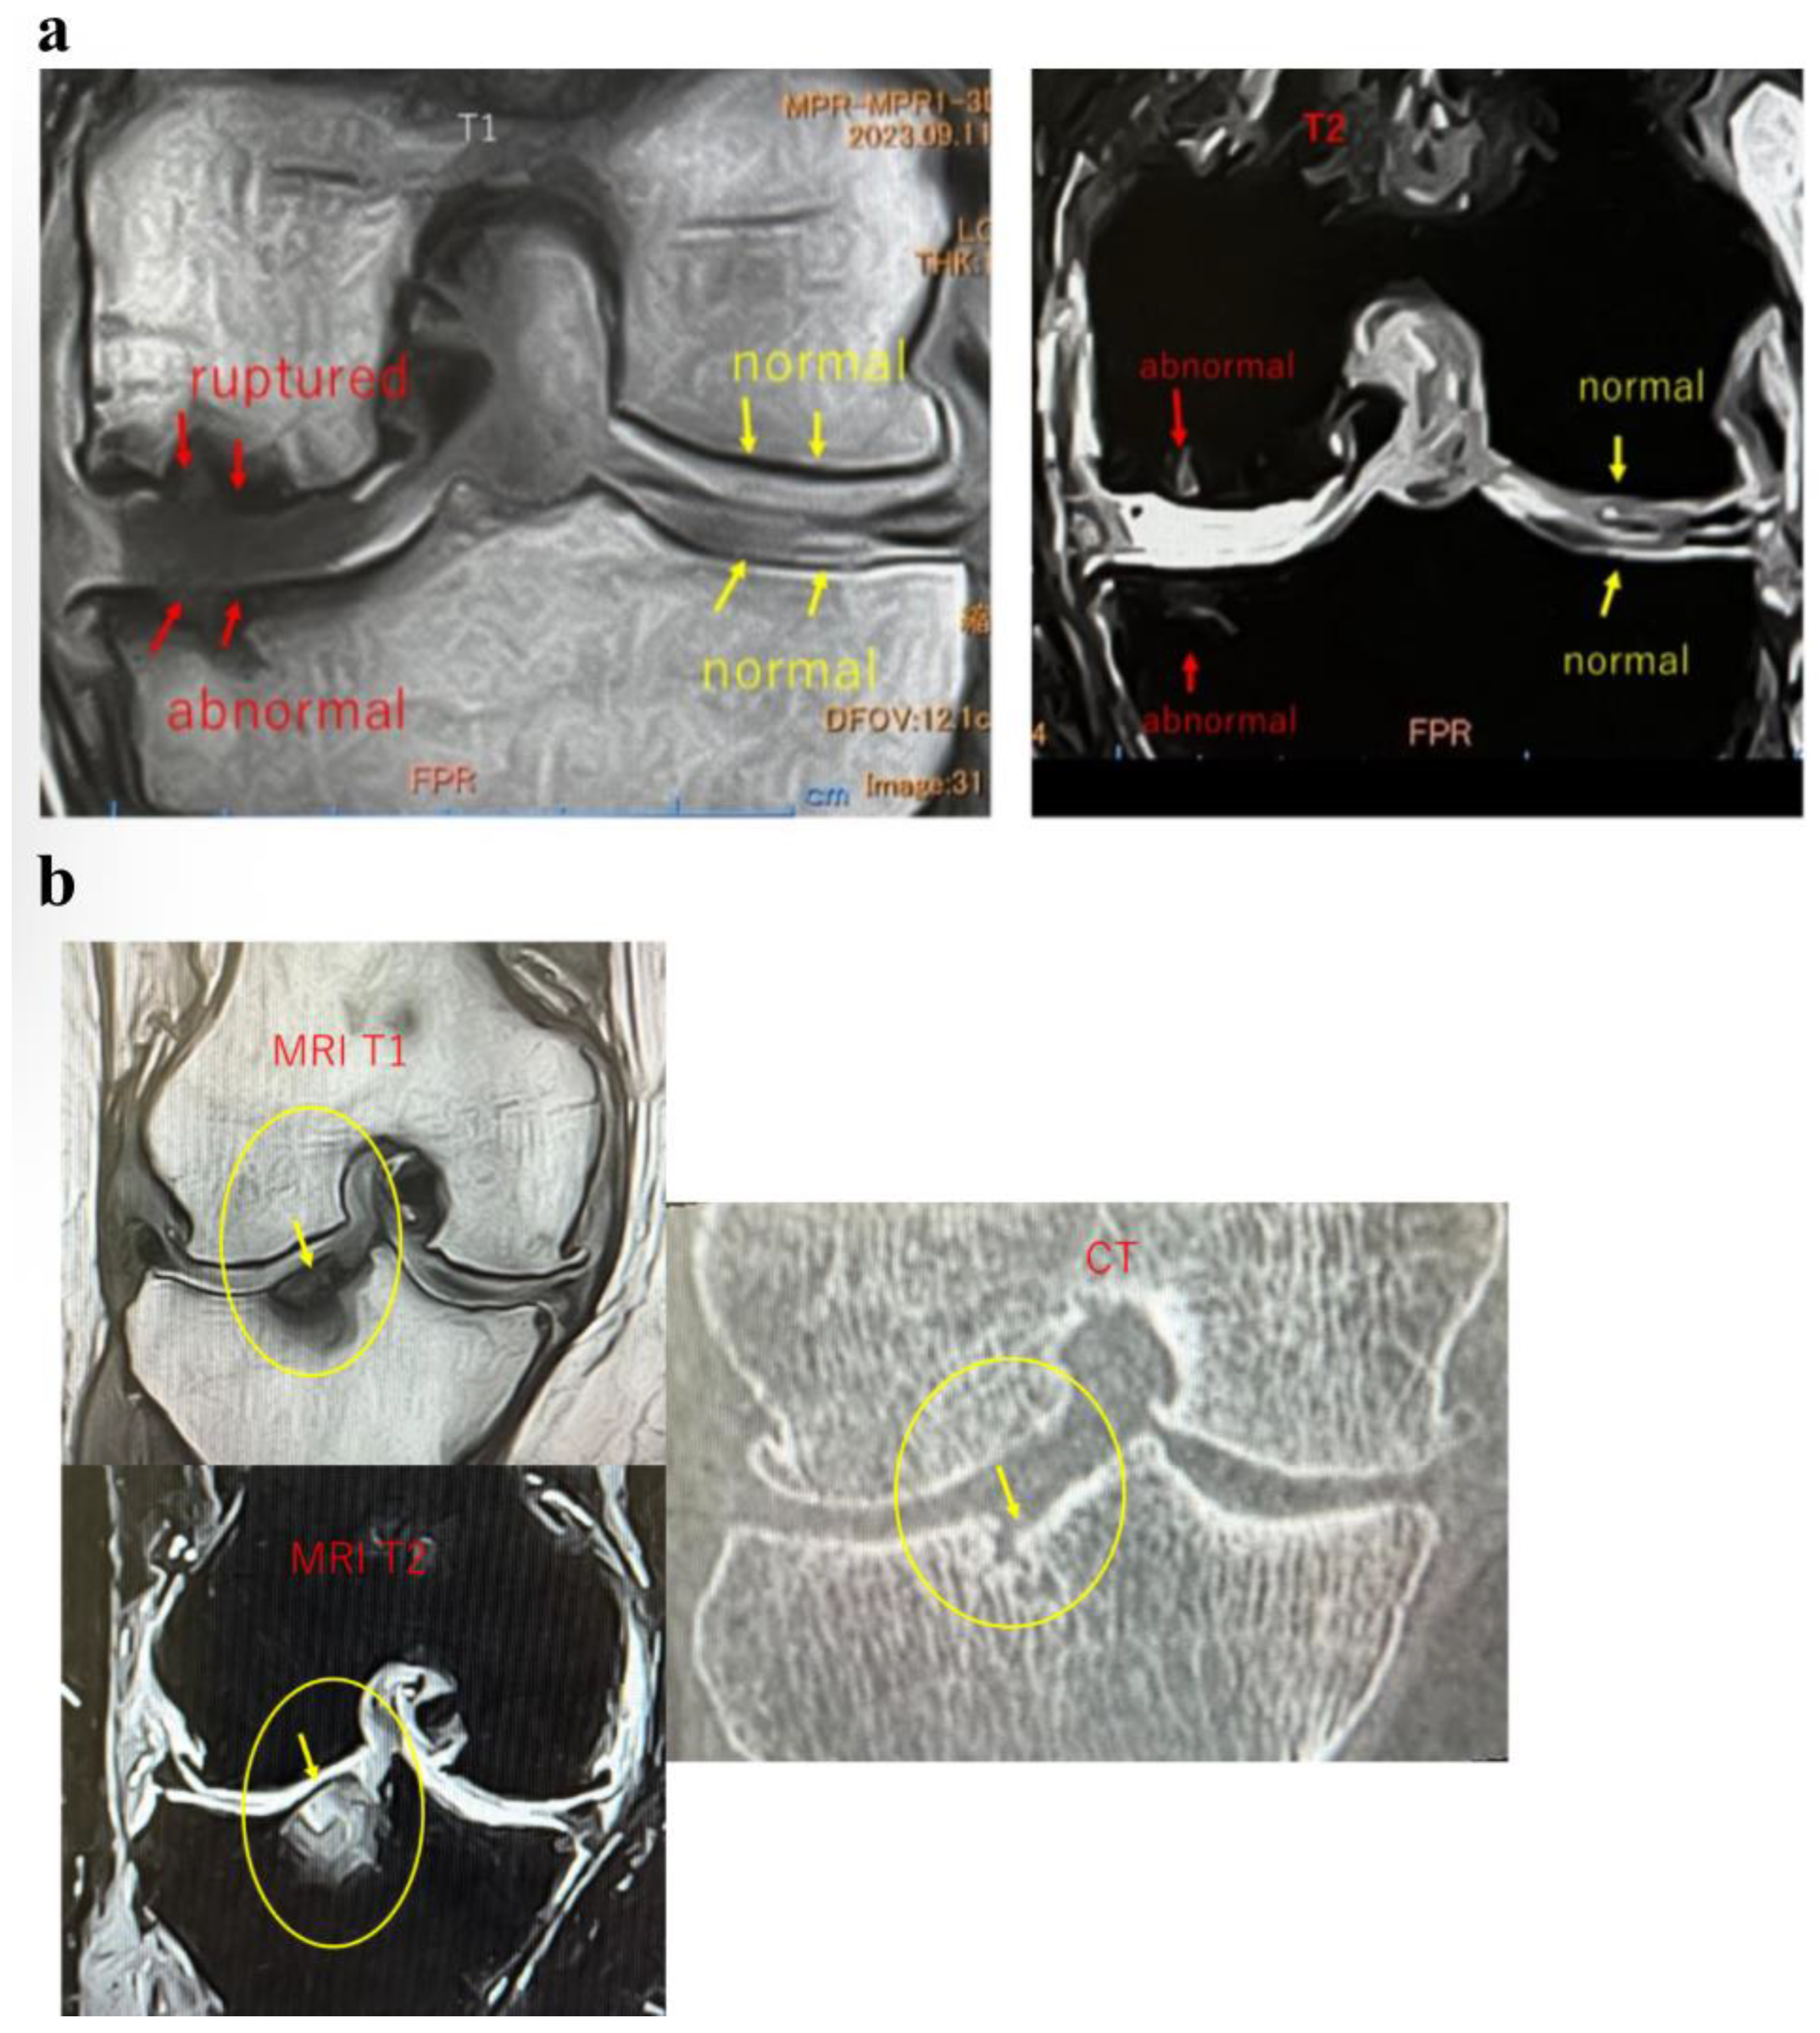

In Case 4 (Figure 9), a 63-year-old male, sequential MRI changes following combined treatment with intra-articular and intraosseous MSC administration and ESWT were evaluated. At baseline, irregularities of the articular surface and a tear of the SBP were observed. At 1 month, early signs of repair became evident, and at 3 months, further progression of structural restoration was noted. At 6 months, near-complete reconstruction of the articular surface and SBP was achieved. These findings suggest that the synergistic effect of MSC administration combined with ESWT may contribute to the regeneration of cartilage and subchondral bone (Figure 9a).

Figure 9.

(a) MRI changes after combined intra-articular/intraosseous MSC administration and ESWT in a 63-year-old male. T1-weighted coronal views (top row) and T2-weighted coronal views (bottom row) at baseline, 1, 3, and 6 months. The targeted area (yellow circles) demonstrated near-complete restoration of the articular surface and SBP at 6 months. (b) Detailed observation of lesions in T2-weighted images. Enlarged views of the joint surface from the T2-weighted images shown in Figure 9a. The BML and articular surface disruption observed pretreatment showed progressive repair at 1 and 3 months, with near-complete restoration achieved by 6 months.

These images (Figure 9b) represent magnified views of the joint surface from the T2-weighted images shown in Figure 9a. Pretreatment findings revealed a BML and disruption of the articular surface. Progressive repair was observed at 1 month and 3 months after treatment. At 6 months, near-complete restoration of the articular surface and SBP was evident.